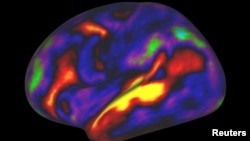

The pattern of brain activation (red, yellow) and deactivation (blue, green) in the left hemisphere when listening to stories while in the MRI scanner is pictured in this undated handout image.

The researchers also used MRI data on cortical activity when people carry out tasks such as listening to stories, computing math problems and looking at other people making various facial expressions.